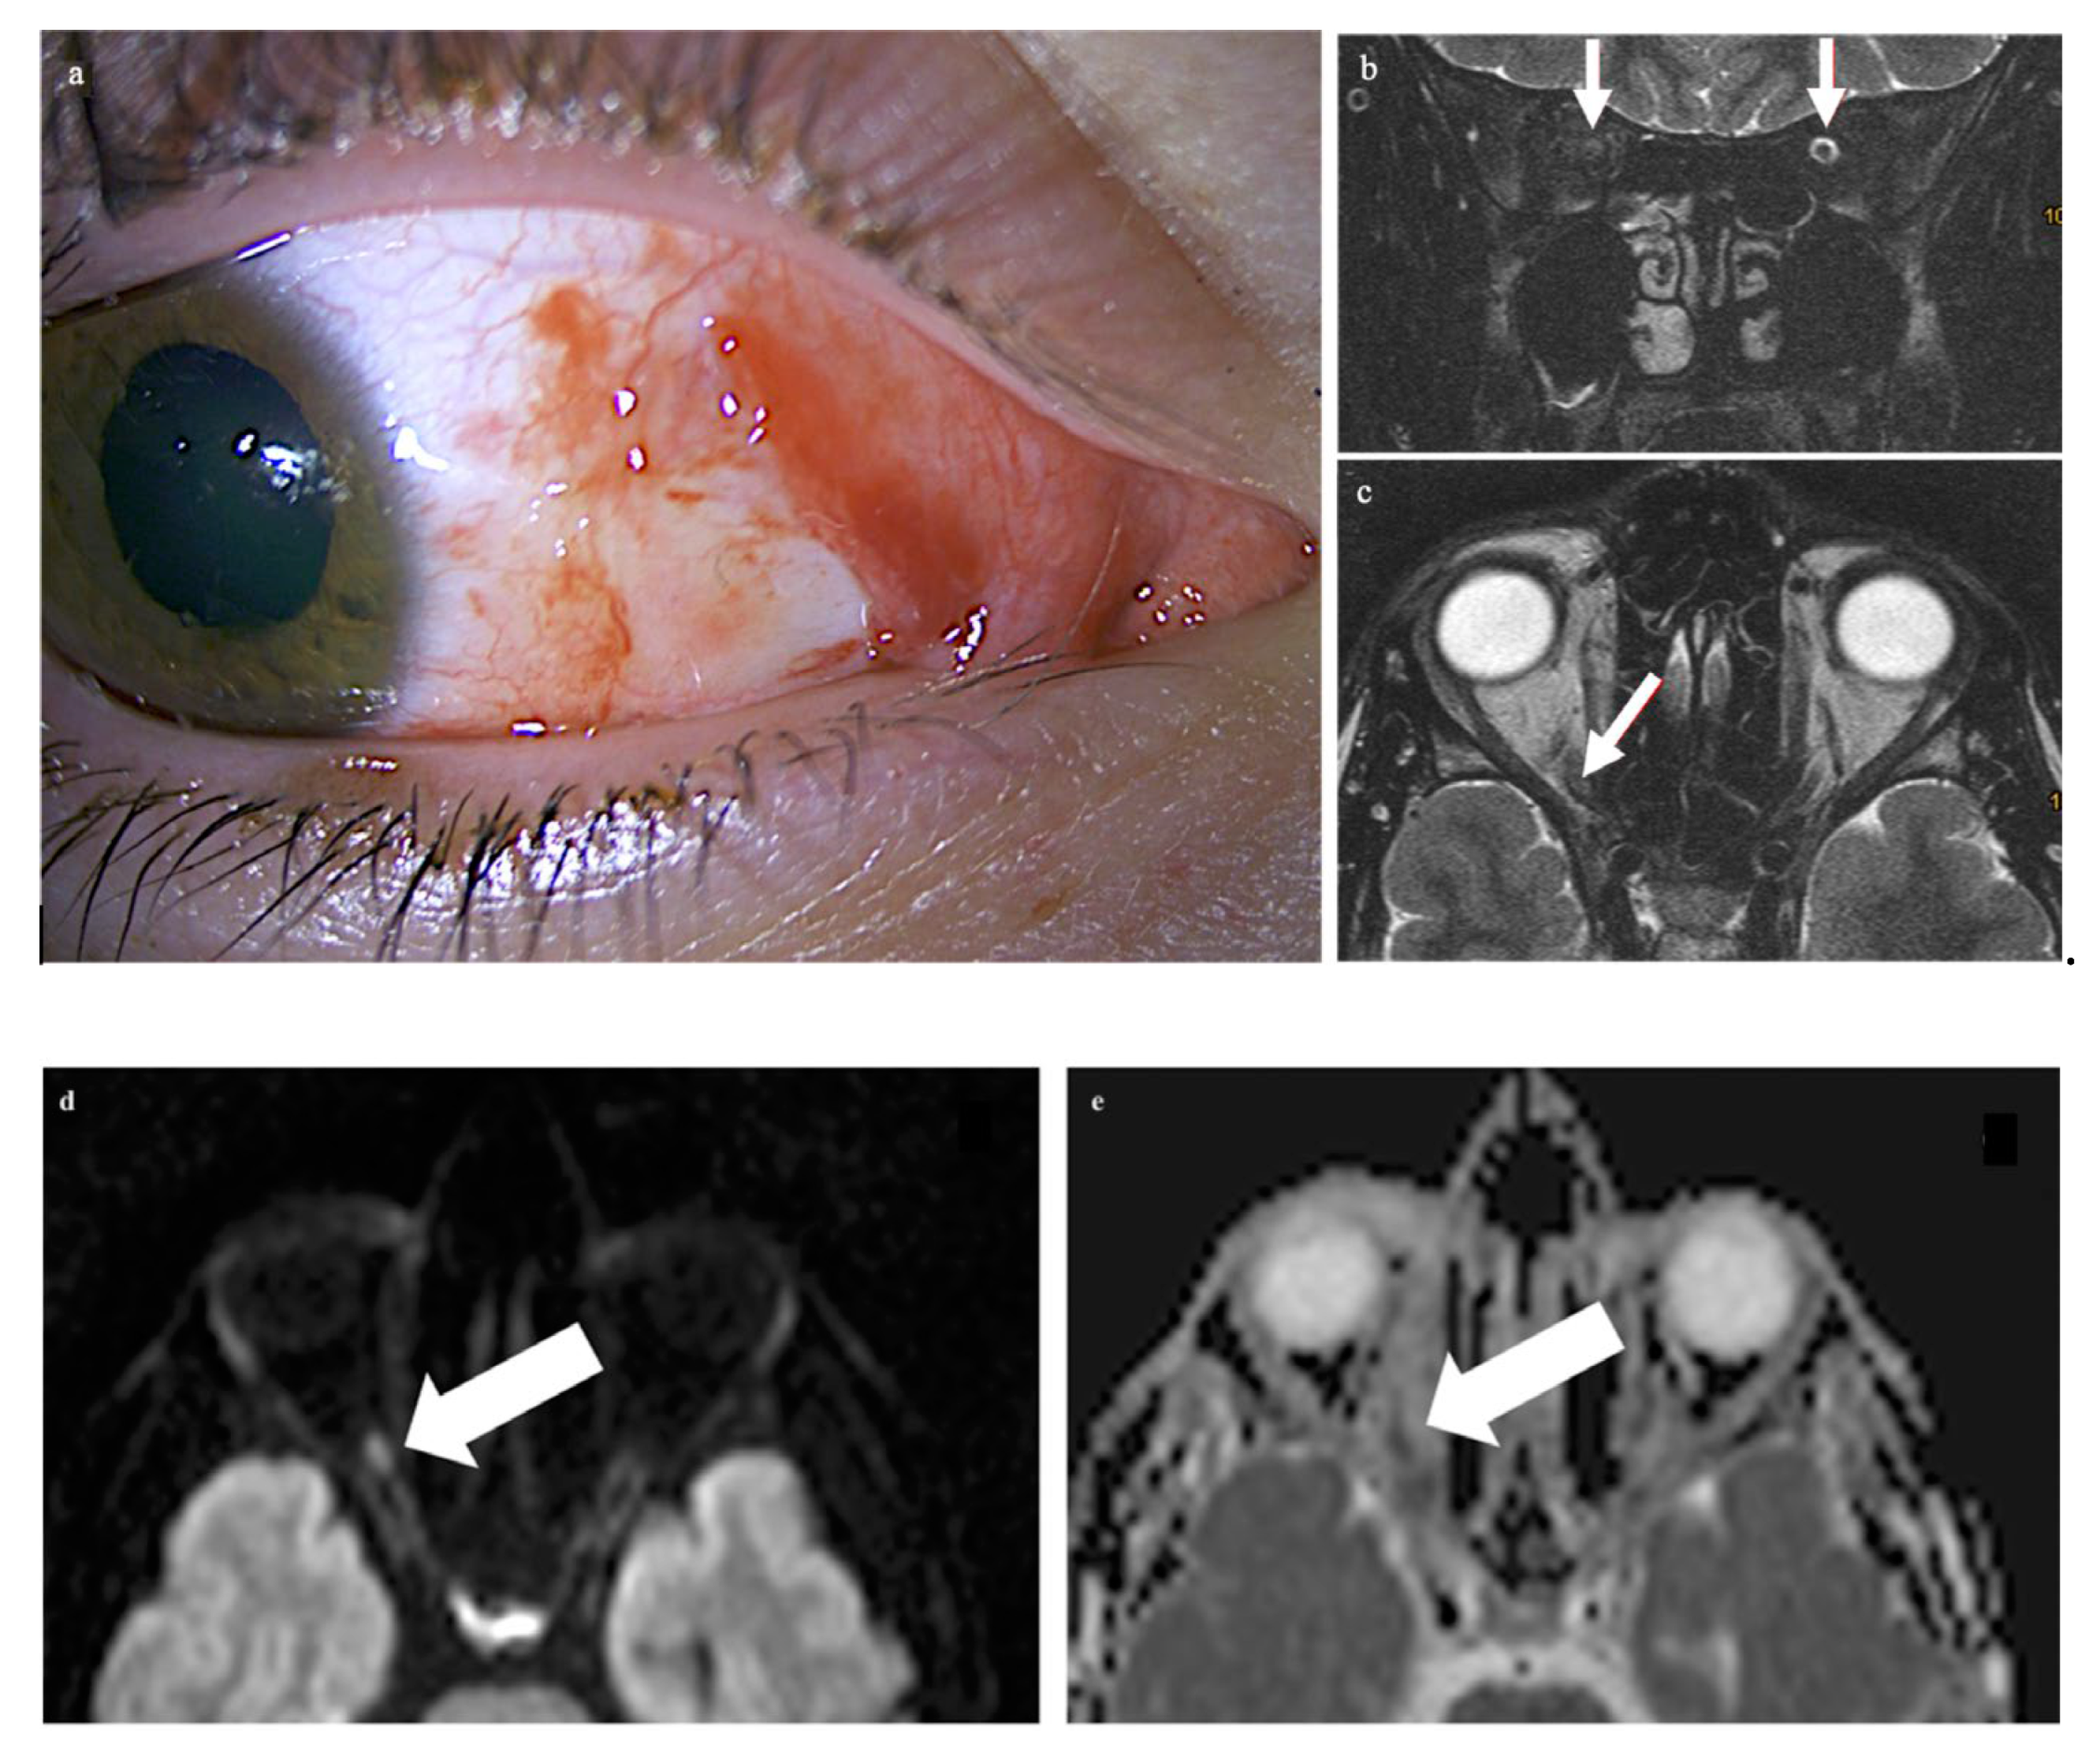

A 21-year-old male patient presented with vision loss in his right eye after trauma. He had injured himself with a metal gardening device and suffered parabulbar penetration of a metal rod into the orbit with only minimal ocular trauma. The metal rod was thin, but with a blunt end; it directly hit and tore into the orbit. Examination of the right eye revealed a superficial conjunctival wound nasally and a dilated pupil (Figure 1a). Ophthalmological examination of the left eye was normal. The globe was not injured. The cornea, lens, retina, and optic nerve head appeared normal upon ophthalmologic examination. Functional ocular examination, however, showed no light perception and a relative afferent pupillary defect.

Figure 1.

Examination of the right eye revealed a superficial conjunctival wound nasally and a dilated pupil (a). On the MRI scan, there is loss of the subarachnoid space in the right optic nerve (arrows in panel (b): the subarachnoid space of the left optic nerve is normal). The respective transverse T2-weighted image shows a central signal increase in the optic nerve (arrow in (c)). On the diffusion-weighted imaging, a punctuate signal increase in the optic nerve in the same location is seen (arrow in (d)); the corresponding ADC map shows signal loss in the same location (arrow in (e)). The globe as well as the left eye and orbit are unchanged, while there is a diffuse signal increase (arrows) in the right retrobulbar space nasally (f,g).

CT of the facial skull showed neither fractures nor foreign bodies, metallic or otherwise (Somatom Excite, Siemens Healthineers, Erlangen, Germany). The optic canal was normal. MR imaging was performed 4 hours after the trauma on a 1.5 T imager (Symphony, Siemens Healthineers, Erlangen, Germany) with a standard head coil. Plain T1w spin-echo images in the transverse orientation (TR 500 ms, TE 8.8 ms) and plain T2w turbo spin-echo transverse and coronal images with and without fat saturation (TR 4.000 ms and TE 128 ms) by prepulse were obtained in a 2 mm slice thickness. For DWI and ADC maps, a transverse orientation was chosen (5 mm slice thickness, TR 2500, TE 80 ms, and b-value of 1.000 s/mm2). Imaging demonstrated on coronary T2-weighted fat-saturated MRI loss of the subarachnoid space in the right optic nerve (white arrows in panel b: the subarachnoid space of the left optic nerve is normal) while the respective transverse T2-weighted image revealed slight optic nerve distention with a central signal increase (white arrow in c) right frontally from the optic canal. Diffusion-weighted imaging showed a punctuate signal increase in the optic nerve in the same location (d); the corresponding ADC map had signal loss in the same location (e). The globe was unchanged, while the retrobulbar space showed a diffuse signal increase nasally (f,g). The left eye and orbit were normal.